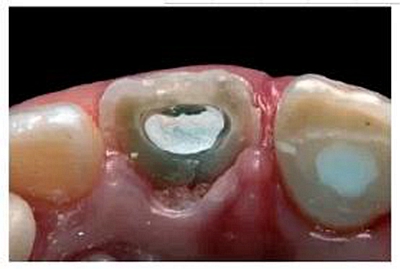

去除殘留的復合樹脂后,輕輕去除10mm長的牙膠,操作時盡量避免損傷薄弱的根管壁。根據(jù)所需長度,選擇6號成品FRCP放入根管內(nèi)。由于根管口較大,樁和根管壁間無法獲得足夠的固位力(圖12)。但填入樹脂粘接劑后,樁和根管壁之間的間隙則不會對FRCP的性能產(chǎn)生較大影響。粘接前需用乙醇清洗纖維樁表面。

根據(jù)前文中的研究結(jié)果,我們決定結(jié)合使用LB和LCZ。根管內(nèi)先進行酸蝕處理。大量無菌蒸餾水沖洗根管,去除磷酸酸蝕劑后,干燥根管。根據(jù)產(chǎn)品說明再度潤濕根管,這一步對重建塌陷的膠原纖維網(wǎng)是非常有必要的,這能確保丙酮類粘接系統(tǒng)的最佳滲透力。根據(jù)產(chǎn)品說明,和應用于牙本質(zhì)一樣,在樁和根管內(nèi)使用PreBond以及BondA和BondB的混合劑。當將LCZ充入根管內(nèi)時,樁和粘接材料充分接觸,使樁表面達到最佳表面潤濕。將FRCP放入根管,去除根管多余樹脂,光照固化(2000 mW cm-2;MiniLED III; Satelec Acteon Equipment, Merignac,F(xiàn)rance)。